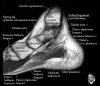

발목 관절의 MRI 단면 영상

- Sagittal section

- Coronal section

- Axial section